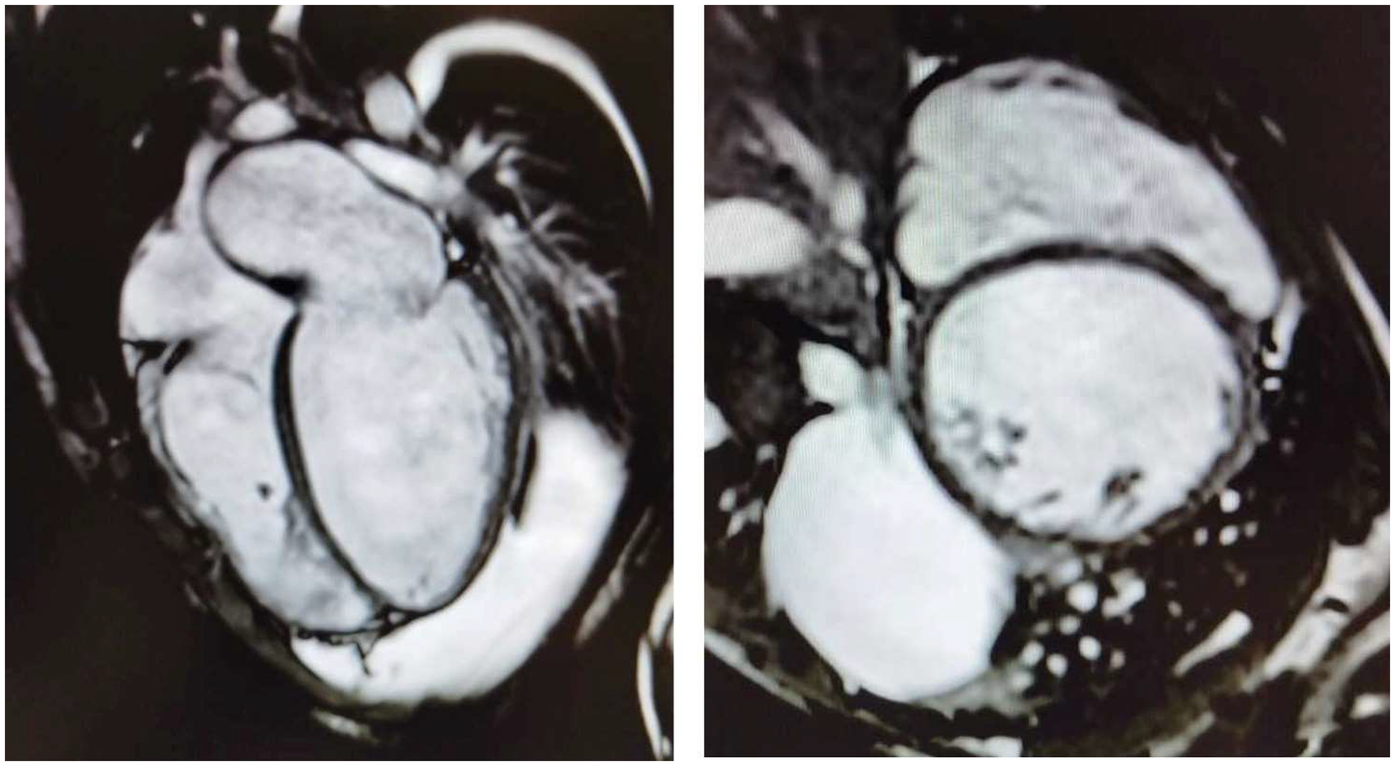

Herein, we describe the cases of two 16-year-old identical male twins who presented with acute end-stage heart failure (HF) requiring emergency heart transplantation (HT), secondary to dilated cardiomyopathy (DCM). The patients provided informed consent for the publication of their cases. The twins, who are the sons of first cousins, were born at term and were previously in good health, had no past medical history, and no cardiovascular or neuromuscular symptoms. They were diagnosed within 15 days of each other and underwent successful HTs within a week of each other. Twin A had been in good health until he developed a worsening cough and dyspnea. Echocardiography revealed a new diagnosis of DCM with severely reduced systolic function. He was transferred to the coronary care unit (CCU), where intravenous milrinone, furosemide, and norepinephrine were administered. Cardiac MRI confirmed severe biventricular dysfunction with myocardial fibrosis (FigureĀ 1). Myocarditis screening was negative. He was diagnosed with acute HF secondary to idiopathic DCM and listed for an HT (status 2). As his clinical condition worsened to refractory cardiogenic shock, he was transferred to the intensive care unit (ICU), intubated, and placed on femoro-femoral veno-arterial extracorporeal membrane oxygenation (VA-ECMO). Due to progressive left ventricular (LV) distention with pulmonary edema, the patient underwent rescue percutaneous atrial septectomy to obtain LV venting. The patient was listed as status 1 and underwent an HT within 24 days. His postoperative course was complicated by pneumothorax, requiring chest tube insertion. He was discharged on postoperative day 40. He experienced a single episode of acute cellular rejection (grade 2R), which was treated with intravenous methylprednisolone. The patient is thriving 3 years after the HT, with preserved biventricular function and no evidence of cardiac allograft vasculopathy (CAV).

FigureĀ 1

Four-chamber (left) and short-axis (right) cine images from cardiac magnetic resonance imaging demonstrating severe bi-ventricular dilatation, accompanied by myocardial wall thinning and fibrosis.